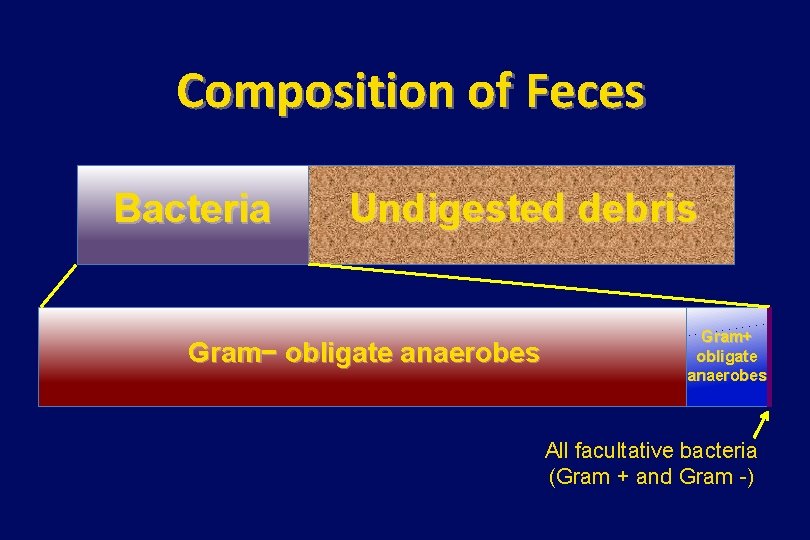

Composition of Feces Bacteria Undigested debris Gram− obligate anaerobes Gram+ obligate anaerobes All facultative bacteria (Gram + and Gram -)